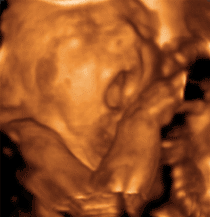

• 3D-Live Baby-Fernsehen

Welche dieser individuellen Gesundheitsleistungen für Sie persönlich wichtig und relevant sind, besprechen Sie bitte mit unserem besonders geschulten Personal oder Ihrem behandelnden Frauenarzt.   -  Jetzt noch 3 Beispiele für unser neues Angebot des 3D-Live-Babyfernsehens!

Genießen Sie es !!